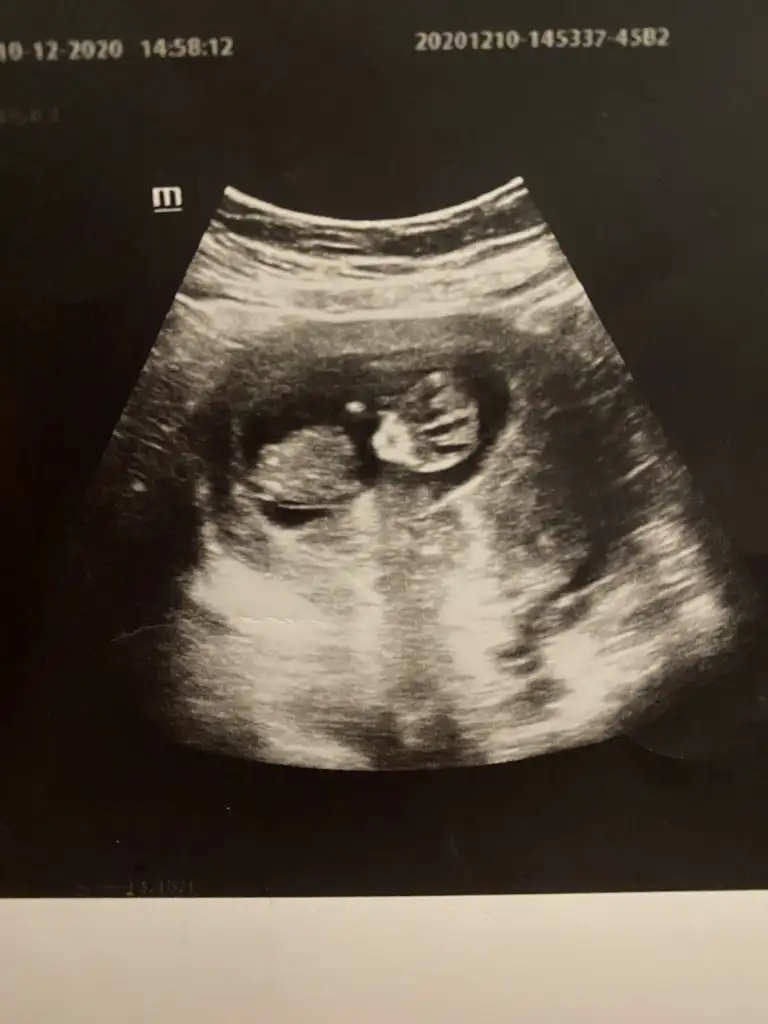

Yaaa benimkini de yorumlar mısınızzzz çok merak ettim

• CADEFB2F-3AB7-40FD-A49B-14D9926058F8.webp

29,1 KB · Görüntüleme: 76